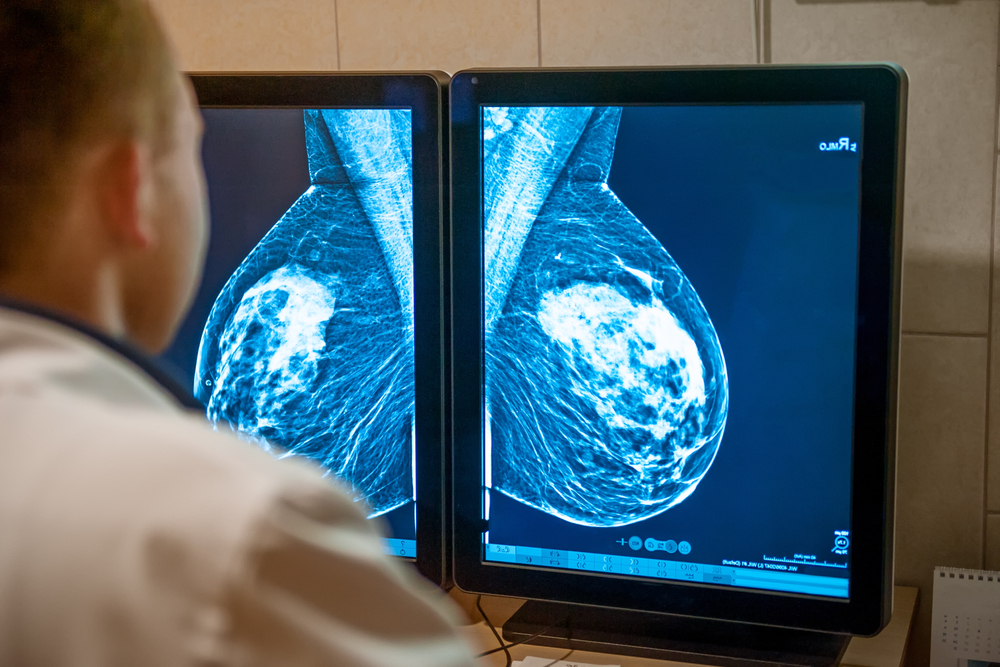

Según un nuevo estudio, un modelo de inteligencia artificial (IA) basado únicamente en imágenes para predecir el riesgo de cáncer de mama a cinco años proporcionó una estratificación del riesgo más sólida y precisa que la evaluación de la densidad mamaria.

Clairity Breast es el primer modelo de IA de riesgo de cáncer de mama basado únicamente en imágenes aprobado por la FDA y fue entrenado en 421,499 mamografías de 27 sitios en Europa, América del Sur y Estados Unidos.

Al utilizar mamografías de mujeres que desarrollaron cáncer y de mujeres que no desarrollaron cáncer durante los siguientes cinco años, el modelo de IA pudo aprender patrones y diferencias en el tejido mamario que predicen el riesgo de cáncer de mama.

El Dr. Lehmann explicó: «Este modelo puede detectar cambios en el tejido mamario que son invisibles para el ojo humano, una tarea que los radiólogos no pueden realizar».

Cuando se tuvo en cuenta la densidad mamaria, las mujeres del grupo de IA de alto riesgo tuvieron más de cuatro veces más incidencia de cáncer que las mujeres del grupo de riesgo promedio (5,9% frente a 1,3%). Por el contrario, la densidad mamaria por sí sola mostró sólo una separación moderada (3,2% para las densas y 2,7% para las no densas).

«Los resultados de este análisis a gran escala muestran que el modelo de riesgo de IA proporciona una estratificación del riesgo mucho más poderosa y precisa para la predicción del cáncer a cinco años que la densidad mamaria por sí sola», dijo el autor principal y presentador Christian Kuhl, jefe del Departamento de Radiología Diagnóstica e Intervencionista del Hospital Universitario RWTH Aachen.